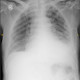

ALO Dokter, ada pasien laki-laki 69 tahun datang ke IGD dengan keluhan sesak nafas sejak yang meningkat dalam 1 hari ini, terutama saat posisi terlentang/tidur dan sesak tersebut menganggu tidur pasien. Saat ini pasien membutuhkan setinggi 2 bantal saat tidur. Apa diagnosis yang tepat ya Dok? EKG dan rontgen terlampir.

Alodokter, kalau dari foto toraks, tampak infiltrat kedua lapang paru, dengan kardiomegali dan efusi pleura kiri --> curiga overload cairan. Jika dari anamnesis dan foto toraks , curiga pasien ini lebih ke ALO / edem paru akut. Mungkin akan membaik dengan pemberian furosemide. Kalau dari EKG, mungkin TS kardio yang lebih paham dok.